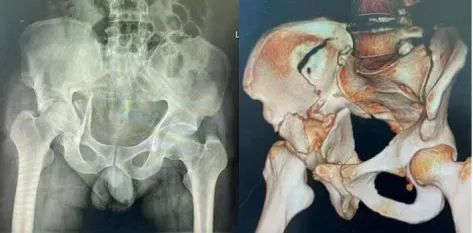

3、中心脱位

股骨头穿透髋臼底,进入盆腔。